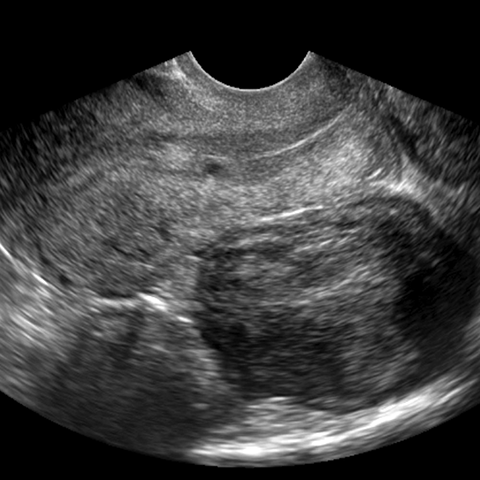

Subserosal leiomyomas [2 of 2]